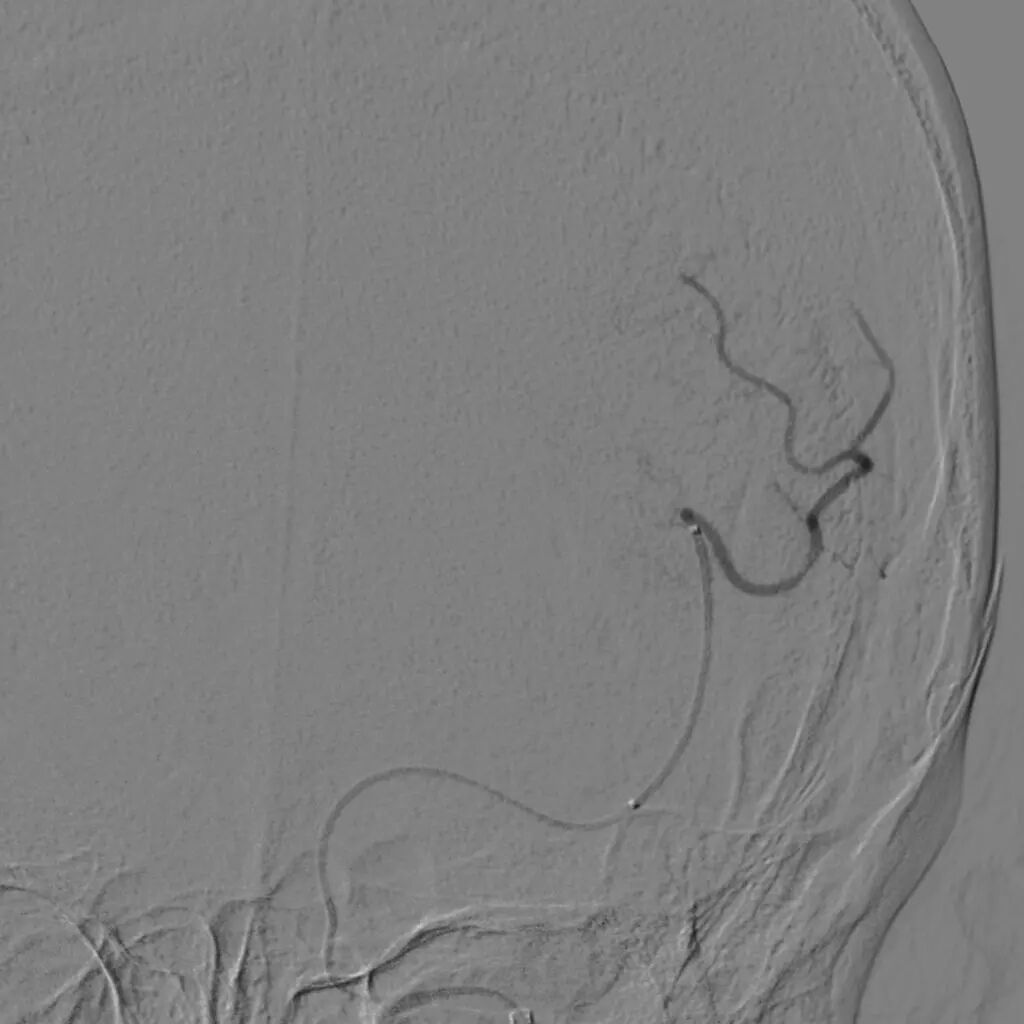

单弯导管辅助长泥鳅导丝置于LC1末端,交换Infinity长鞘至LC1,DSA:LM闭塞。

catalyst 6抽吸导管、Trevo pro-18、Synchro2同轴经长鞘送入,catalyst头端置于LC6,微导丝通过大脑中动脉M1闭塞至M2远端,跟进微导管造影确定血管真腔。

4*20mm Trevo ProVue取栓支架释放,5分钟后抽拉结合取栓,一次取栓,大脑中动脉完全再通。

大脑中动脉完全再通。